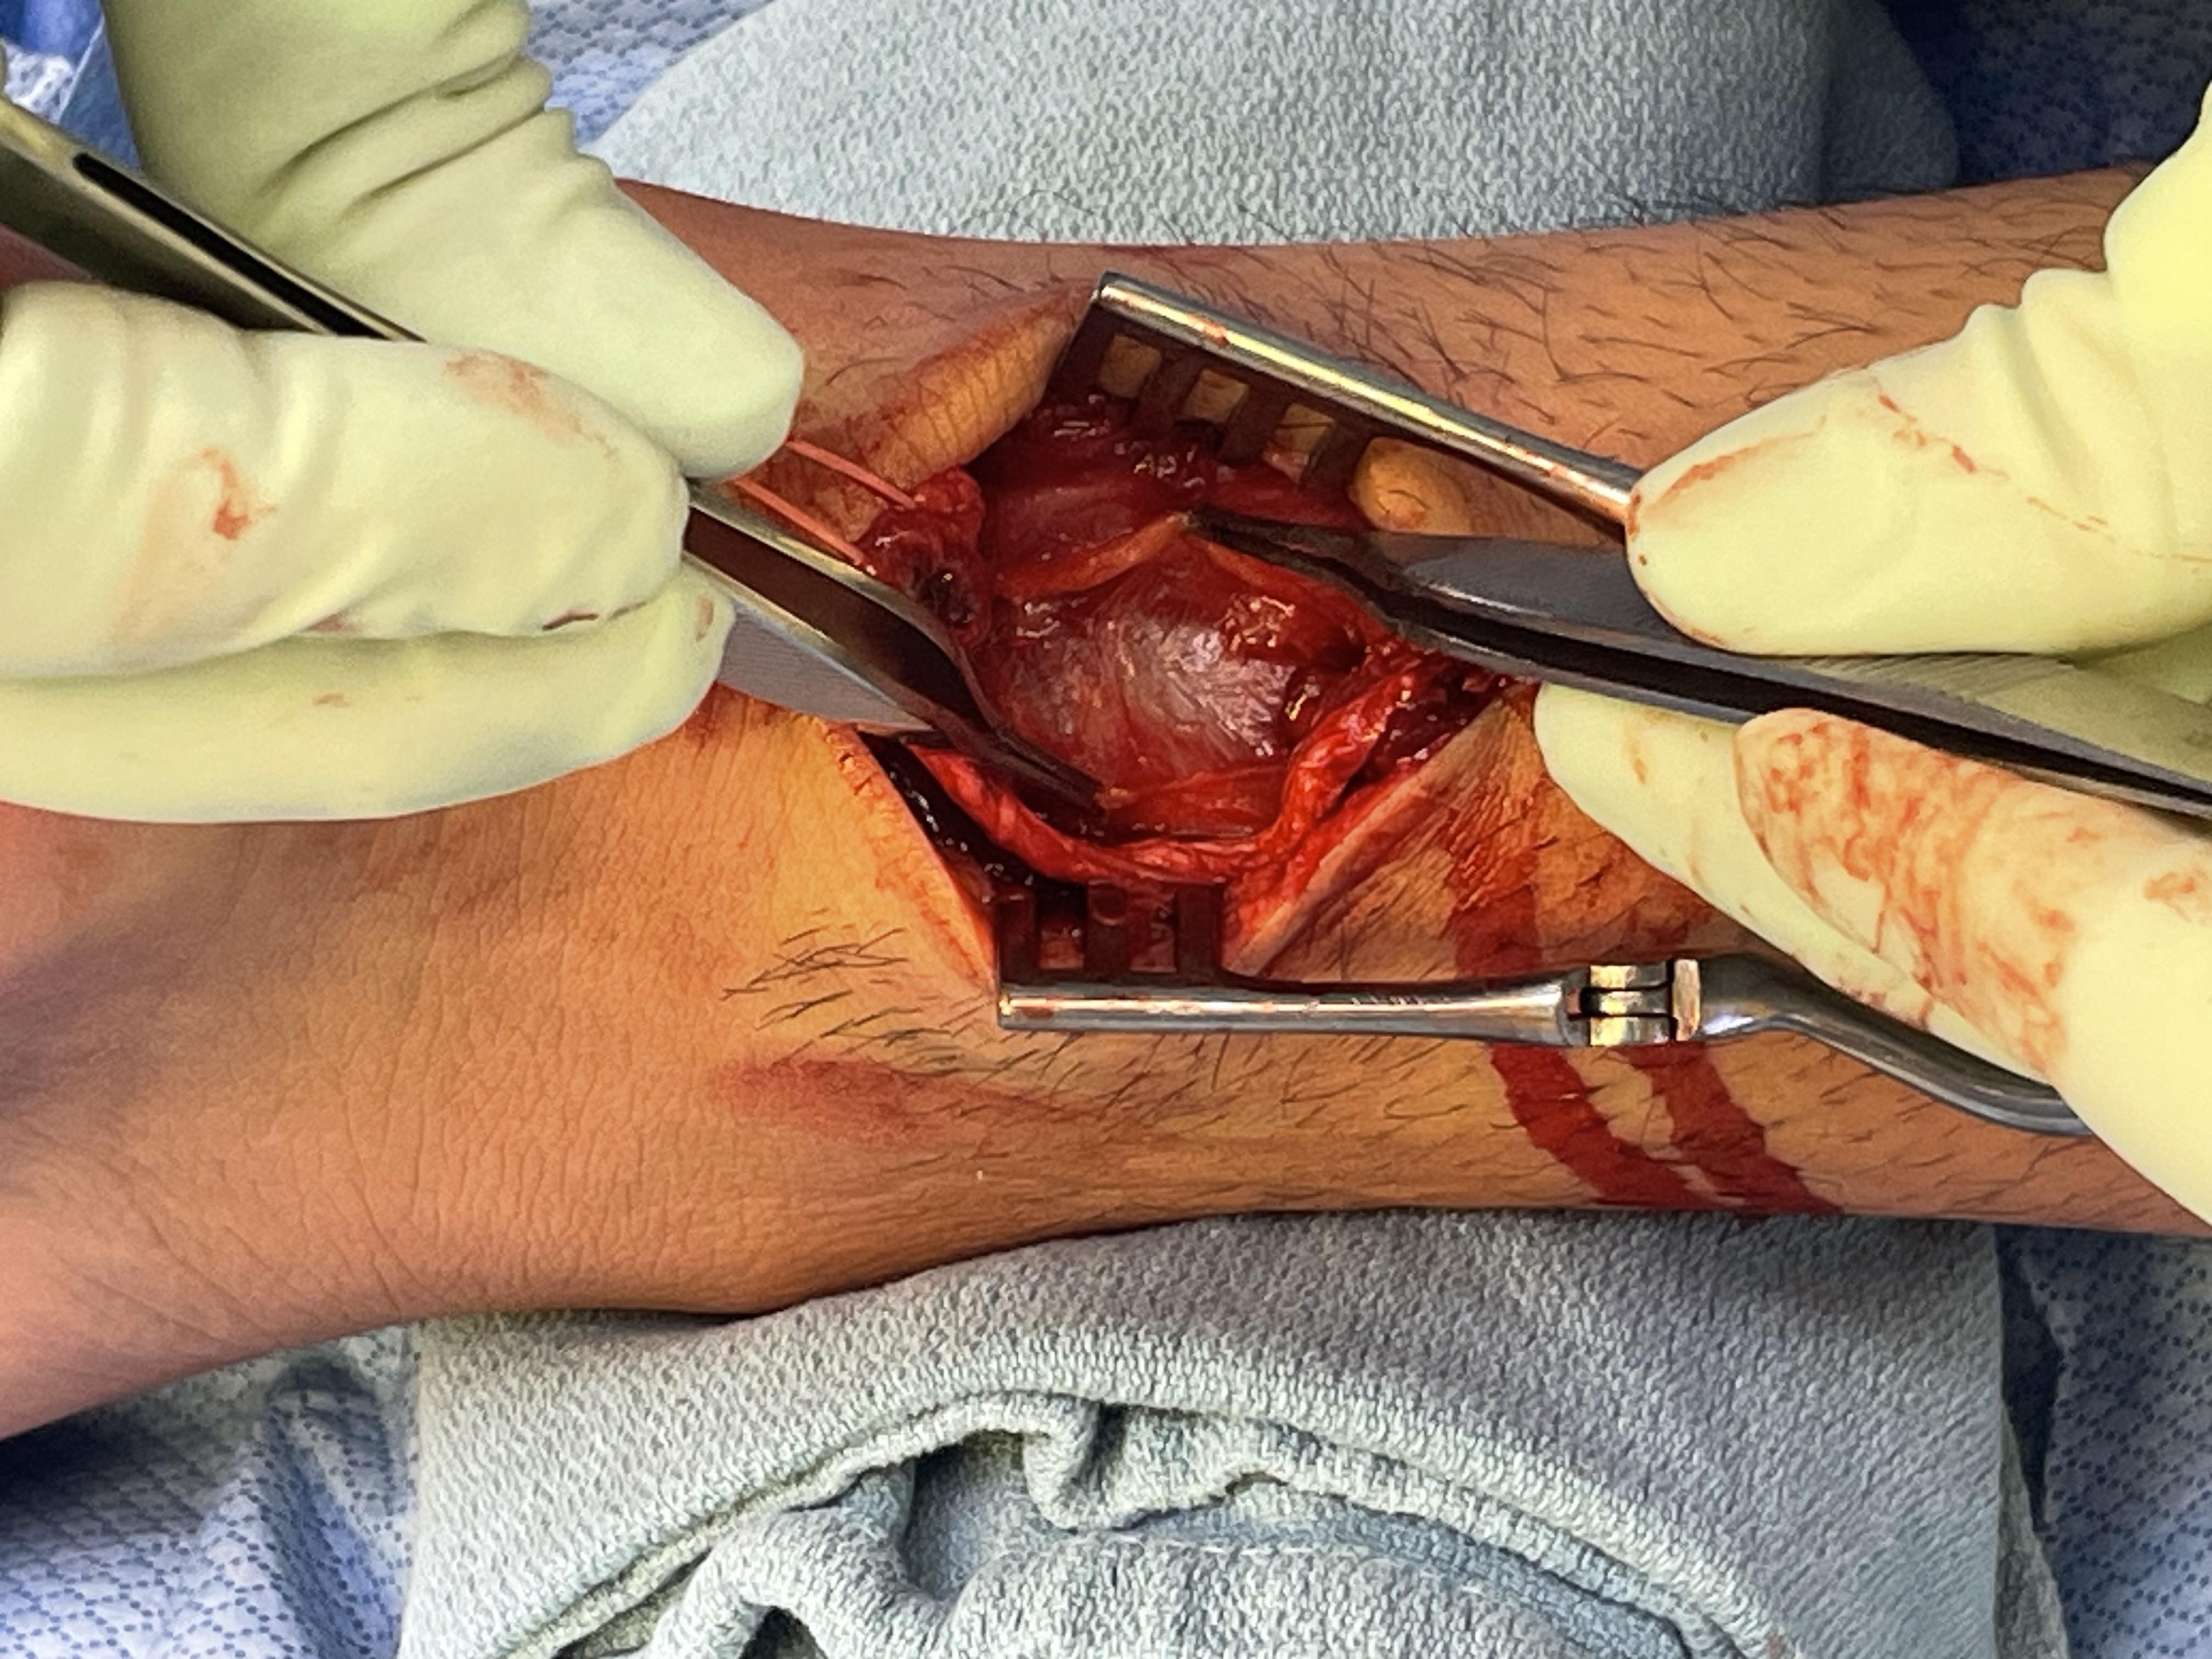

Open tendoachilles repair

Technique

Vumedi open achilles tendon repair

Prone position with tourniquet

- slightly medial incision to protect sural nerve

- full thickness skin flaps to paratenon

- identify and protect sural nerve

- divide paratenon longitudinally

- can incise paratenon in the midline anteriorly which increases tissue available for closure

- Bunnell Suture / Krackow suture x 2 with high strength suture / fibre wire

- one in proximal and one in distal tendon ends

- tie via two knots with foot fully plantar flexed

- +/- augment with circumferential 4.0 suture to minimize bunching

- careful closure of paratenon to prevent skin adhesions

- front slab in plantarflexion 2 weeks

- then standard accelerated rehabilitation

Anterior release of paratenon to allow posterior closure over achilles repair

Repair with proximal and distal Krackow high strength sutures